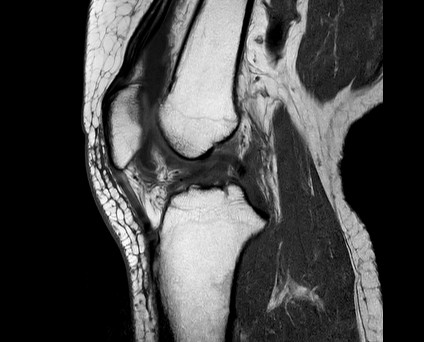

整形領域の撮影

当センターでは、体幹部のみならず四肢の撮影も行っております。膝関節、肩関節、手関節、足関節など整形領域の撮影も行っております。最新のAI技術を用いることで、より細かく描出できるようになり、靭帯損傷や骨折、筋損傷を見つけることが出来ます。

『膝関節MRI画像』